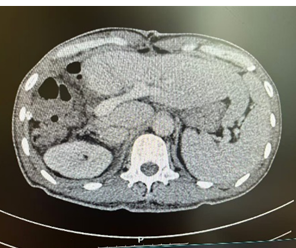

新辅助治疗前CT

由于病人一般情况较好,肝功能良好(Child-pugh A级),经多学科会诊临床确认肿瘤为IIb期肝细胞癌,属于可切除性肝癌,但存在高危复发因素,建议先行新辅助治疗后手术切除。经两次肝动脉关注化疗(HAIC)(奥沙利铂+5-Fu+亚叶酸钙方案)和两个周期的靶向免疫治疗(仑伐替尼+帕博利珠单抗方案),第二次介入造影是肿瘤血供不明显,第二次介入治疗4周后复查CT提示肿瘤缩小不明显但坏死征象明显,经MRI证实仍有少许血供,于是经多学科会诊后决定行前入路右半肝切除术。